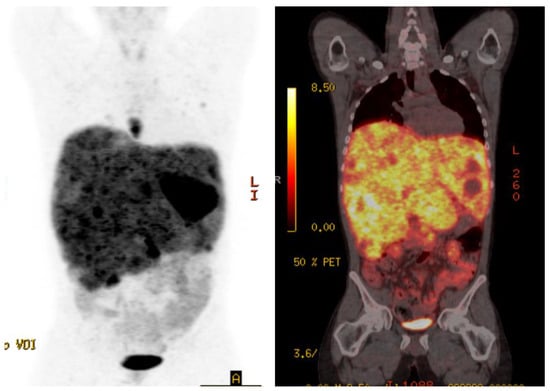

4. Case 3

A 45-year-old previously healthy male presented with episodic fevers and lower back pain, along with 10 kg intentional weight loss. Initial CT scan showed a large pelvic mass with retroperitoneal adenopathy and ipsilateral ureteric compression. Biopsy of the pelvic mass demonstrated a paraganglioma, with a Ki-67 of 30–40%. Given the rapid progression of disease, he received six cycles of carboplatin and etoposide first-line for six cycles. His pelvic pain, fevers and night sweats improved after the third cycle but recurred within one month of discontinuing chemotherapy. A Gallium-68 PET-CT was performed to determine eligibility for PRRT and documented heterogeneous uptake of a large dominant pelvic mass and extensive retroperitoneal adenopathy, Krenning score 4 (Figure 2A). The remainder of his imaging revealed extensive new onset right sided hydronephrosis and left supraclavicular adenopathy. The patient initiated second-line therapy with PRRT, prior to which he was started on prazosin 2 mg twice daily and atenolol 25 mg once daily. Symptoms significantly improved by the second cycle of PRRT and a total of four planned treatments of Lutetium-177 Dotatate, 7.4 GBq (200 mCi), were given without adverse reaction. A radiographic partial response to therapy was documented on follow-up Gallium-68 Dotate PET-CT (Figure 2B) and he discontinued both alpha and beta-blocker therapy until 8 months after PRRT treatment began, when his symptoms recurred and he was diagnosed with progressive retroperitoneal metastasis.

Figure 2. Case 3, (A) Baseline Gallium-68 Dotatate PET-CT demonstrated a large pelvic mass with retroperitoneal adenopathy and ipsilateral ureteric compression; (B) Follow-up Gallium-68 Dotatate PET-CT after 3 cycles of Lu-177 Dotatate demonstrated significant reduction in pelvic mass and retroperitoneal adenopathy.